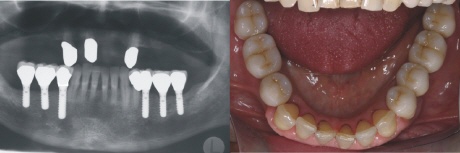

Versorgung

Nach der Einheilphase der Implantate wurden sechs einzelne Kronen auf die Implantate zementiert. Das rechte Bild zeigt die Situation im Mund in der Aufsicht. Die einstmals verkürzten Zahnreihen sind nun vollständig wiederhergestellt.